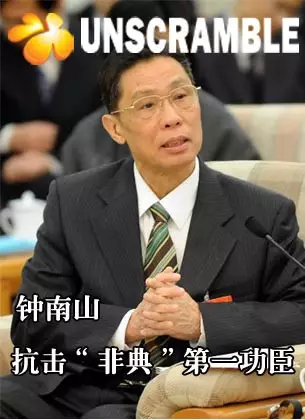

(2)骨坏死:最常见的是股骨头坏死,也可发生膝关节周围的胫骨、股骨及肱骨头等骨坏死,其机理尚未完全清楚。目前研究表明,糖皮质激素导致股骨头坏死的主要原因是血流减少,激素可以通过多种途径引起血流减少,包括骨髓脂肪细胞增生压迫静脉窦,静脉狭窄,甚至静脉堵塞,或脂肪微血栓或含脂肪血小板造成动脉栓塞。其次是糖皮质激素抑制成骨细胞发育和增殖,逆转正常成骨过程,加快破骨细胞代谢(图2)。

图2 激素导致股骨头坏死示意图

通过解读《新冠肺炎诊疗方案》第六版,我们可以得出,此次抗击新冠肺炎,只是对于重型、危重型出现呼吸窘迫综合症的患者,需要大剂量激素治疗以稳定病情,但对激素的使用剂量及时间提出明确要求,而非“尽早、大剂量、长时间使用激素”,所以此次战“疫”过后,理论上股骨头坏死的发生率应该低于非典时期。但也需要疫情结束后进一步验证。对于需要大剂量激素治疗的患者,病情改善或稳定后,要及时调整激素剂量或停药。激素治疗期间应注意预防股骨头坏死,建议应用改善微循环药物,口服降脂药、二磷酸盐、维生素D及钙片。对出现关节疼痛的患者,尤其是髋关节前方腹股沟区疼痛,应及时进行MRI检查,早发现,早拄拐,早治疗,可口服前列环素类药物、抗凝药、降脂药、二磷酸盐,配合高压氧、冲击波等非手术治疗。若股骨头坏死非手术治疗效果不佳,股骨头塌陷前(MRI提示股骨头坏死系I/II期-图4)可以行保髋治疗,包括:髓芯减压术、植骨术和截骨术(图5-7),其中髓芯减压和植骨术可通过微创手术完成。但一旦X线出现新月征(III期-图8)及股骨头塌陷、变形(IV期-图9),最终只能行髋关节置换手术(图10)。

图4 MRI提示:股骨头坏死II期,出现囊性及硬化病灶